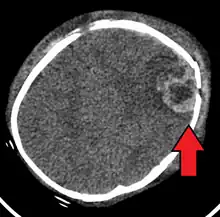

| An intraparenchymal bleed with overlying skull fracture from shaken baby syndrome | |

| Diagnostic method | CT scan[1] |

Shaken baby syndrome (SBS), also known as abusive head trauma (AHT), is a medical condition in children younger than five years old,[3] generally caused by blunt trauma, vigorous shaking, or a combination of both.[1] SBS is the leading cause of fatal head injuries in children under two,[4] with a risk of death of about 25%.[3] The most common symptoms include retinal bleeds, multiple fractures of the long bones, and subdural hematomas (bleeding in the brain).[5]

The condition is often caused as a result of a parent or caregiver becoming frustrated due to the child crying.[3] Diagnosis can be difficult as symptoms may be nonspecific.[1] A CT scan of the head is typically recommended if a concern is present.[1] If there are concerning findings on the CT scan, a full work-up for child abuse should occur, including an eye exam and skeletal survey. Retinal hemorrhage is highly associated with AHT, occurring in 78% of cases of AHT versus 5% of cases of non-abusive head trauma.[6][7]

Diagnosis can be difficult as symptoms may be nonspecific.[1] A CT scan of the head is typically recommended if a concern is present.[1] It is unclear how useful subdural haematoma, retinal hemorrhages, and encephalopathy are alone at making the diagnosis.[25]